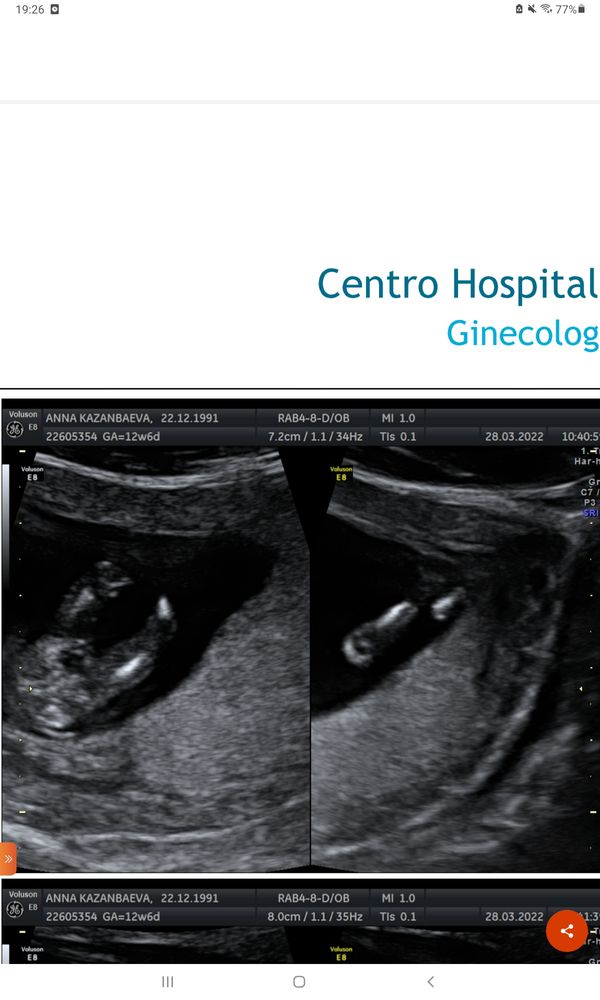

Мальчик или девочка?🙏❤🙂

Изображение На мальчика похоже. Сейчас покажу как у меня, сказали девочка...

Узнать пол по крови Половой бугорок